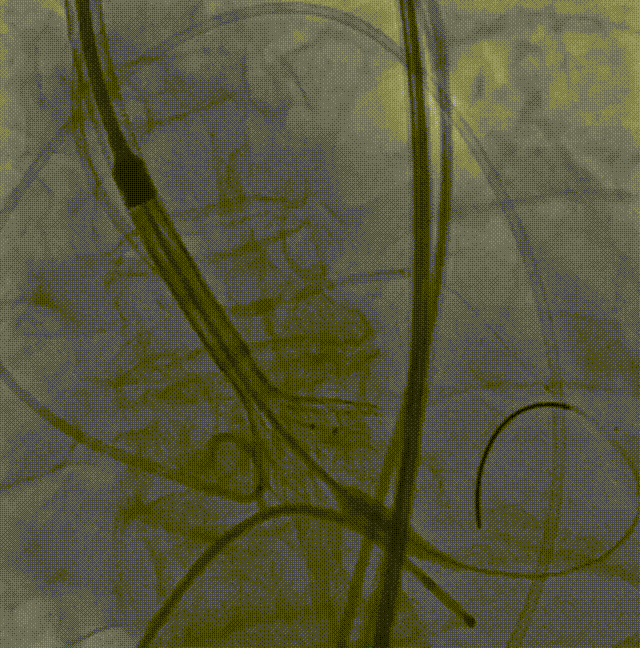

瓣膜内22mm球囊后扩张,左冠无显影

LM烟囱支架植入4.0*30mm